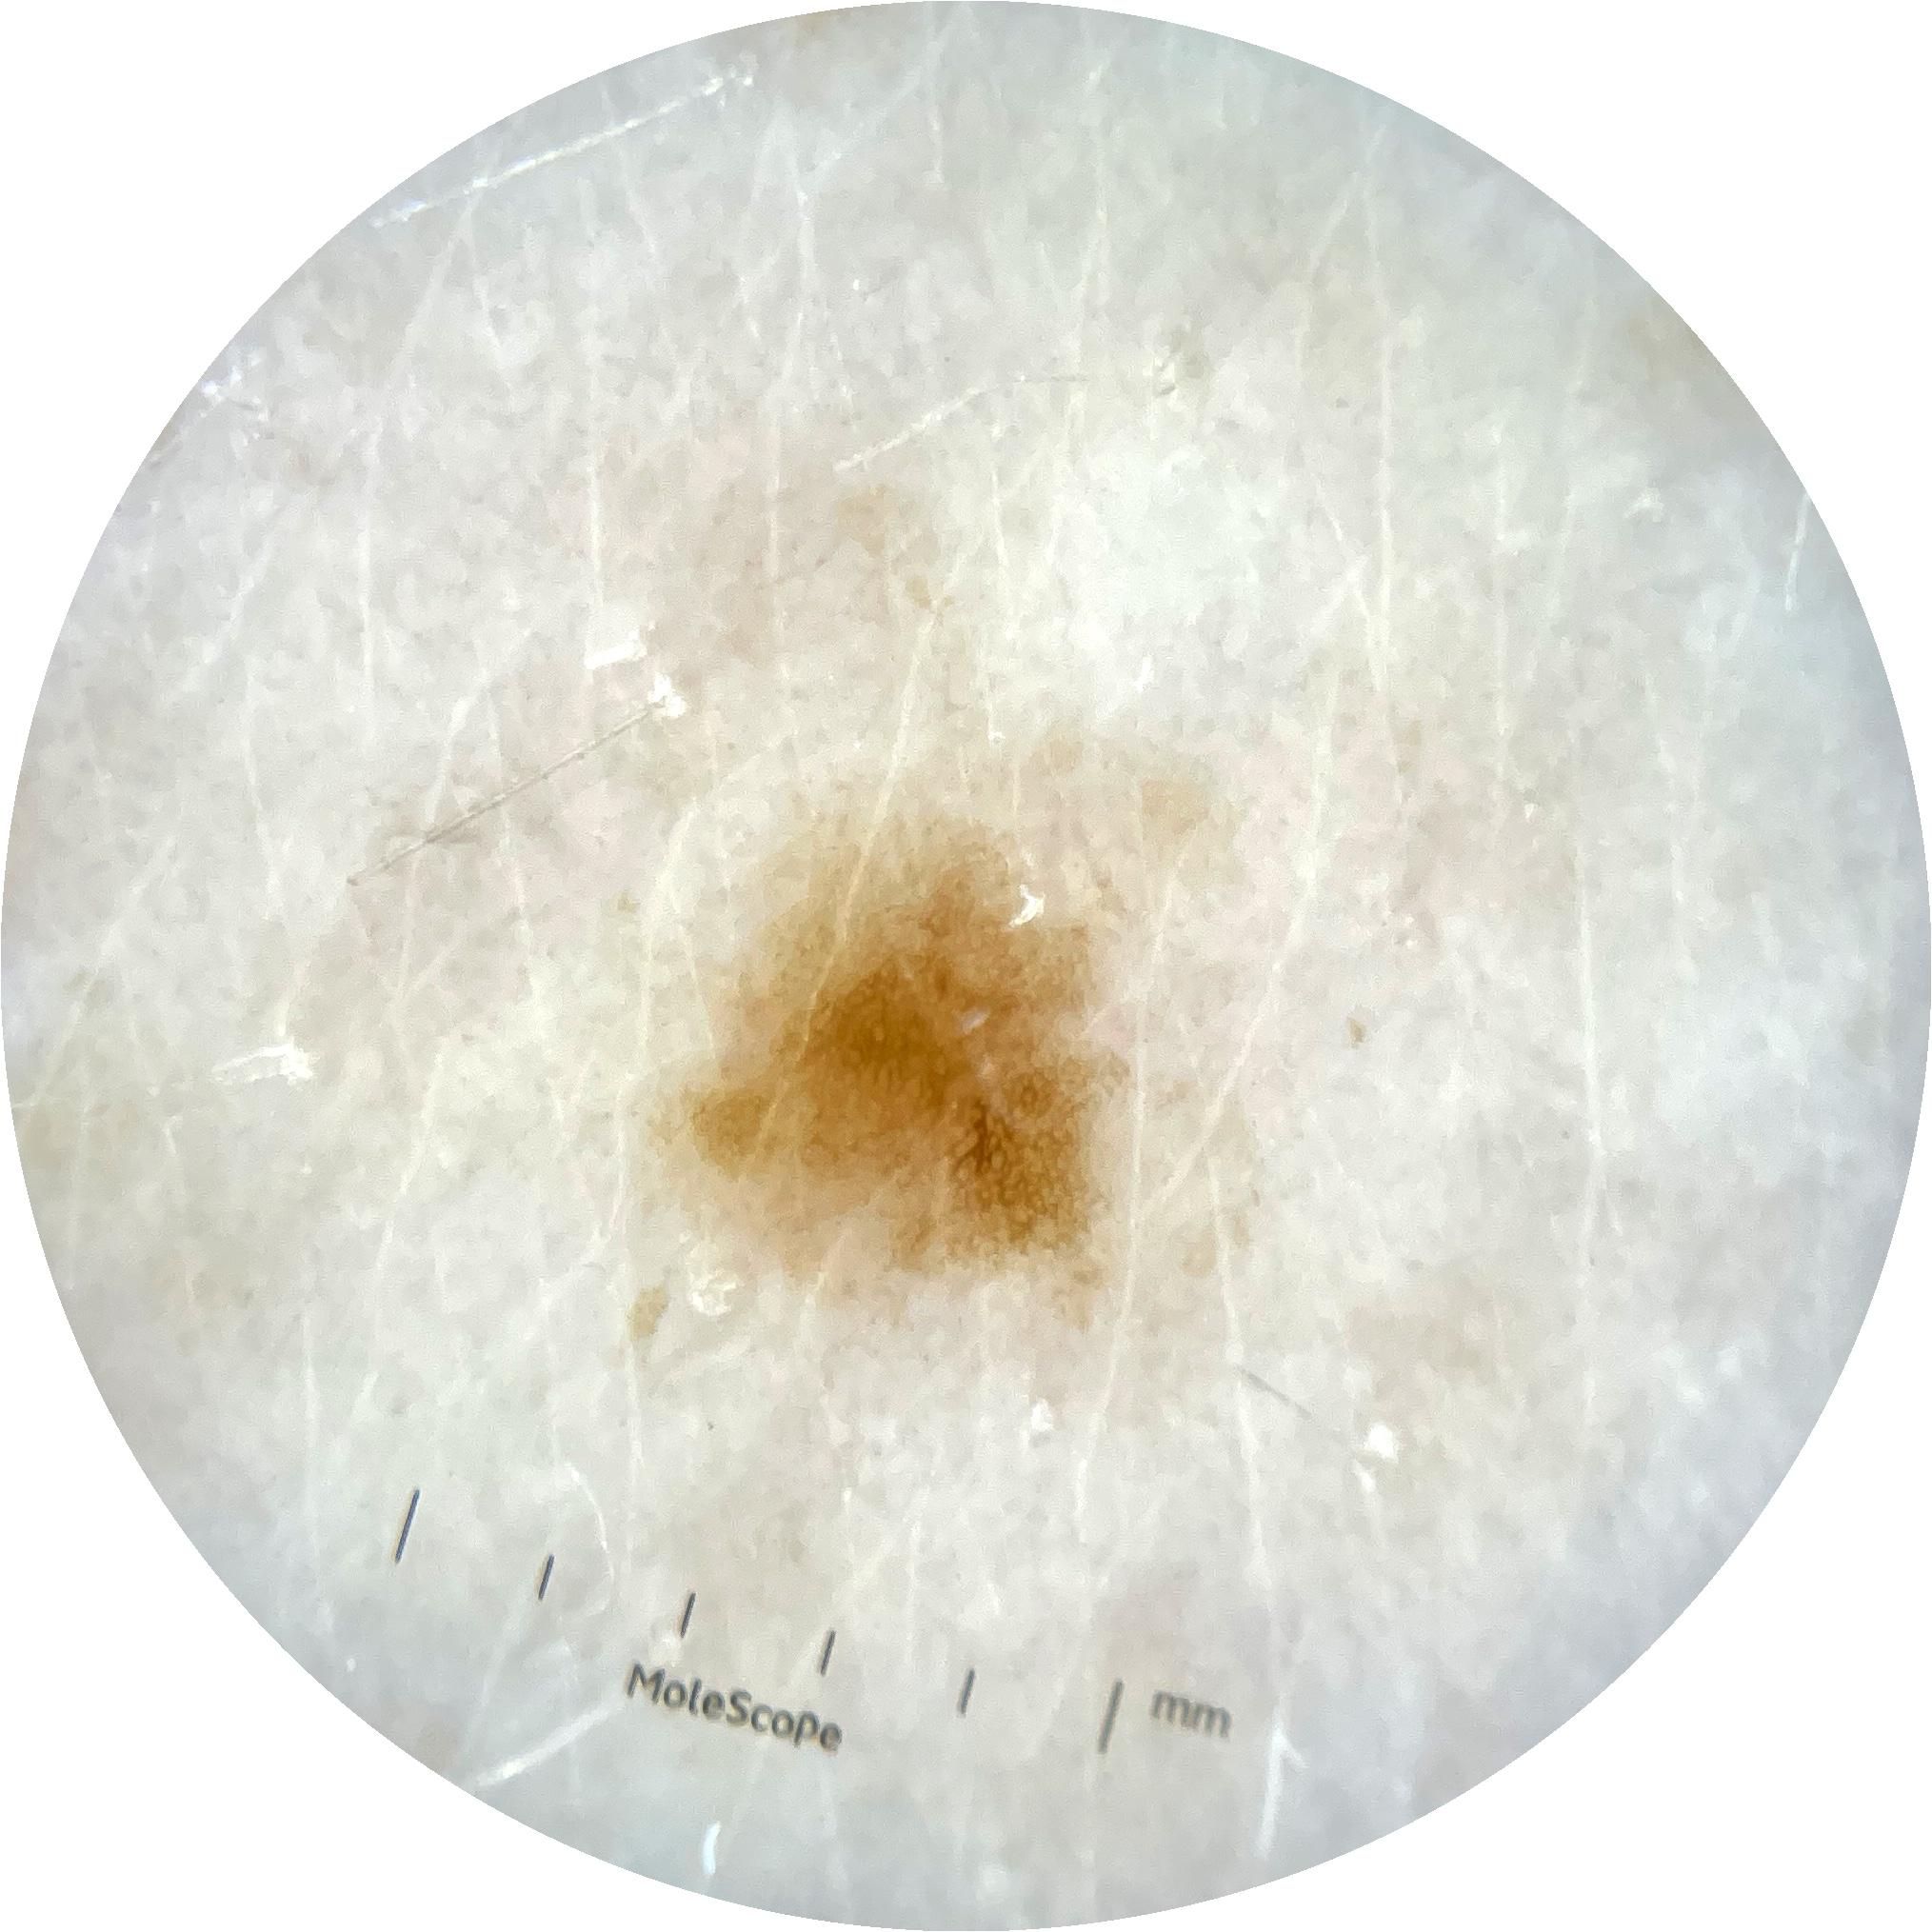

ISIC_9785574

Information

2003 x 2003

Attribute to

MEL-SELF Trial, https://www.sydney.edu.au/medicine-health/our-research/research-centres/melself-project.html

Field Value

acquisition_day 148

age_approx 45

anatom_site_1 Head and neck

anatom_site_general head/neck

concomitant_biopsy False

diagnosis_1 Benign

diagnosis_confirm_type single image expert consensus

family_hx_mm True

image_manipulation instrument only

image_type dermoscopic

lesion_id IL_0236417

patient_id IP_8456088

personal_hx_mm True

sex female